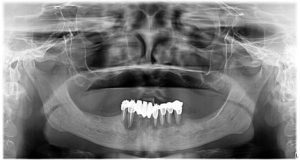

Doamna Filip a avut parte la clinica DentOP de cea mai complexă reabilitare orală, utilizând implanturi zigomatice.În urma unei consultații cu Dr. Cazacu Corrado, s-a constatat o retracție osoasă severă la nivelul maxilarului, făcând imposibilă utilizarea implanturilor convenționale pe termen lung. Radiografia atașată mai jos ilustrează situația clinică inițială.

Implanturile zigomatice sunt un tip special de implant dentar, conceput pentru pacienții cu pierdere severă de os maxilar. Aceste implanturi sunt mai lungi decât cele convenționale și sunt ancorate direct în osul zigomatic (osul pomeților), oferind o soluție stabilă și durabilă pentru fixarea protezelor dentare. Puteți vedea pe radiografia panoramică a pacientei cum arată implanturile zigomatice inserate.